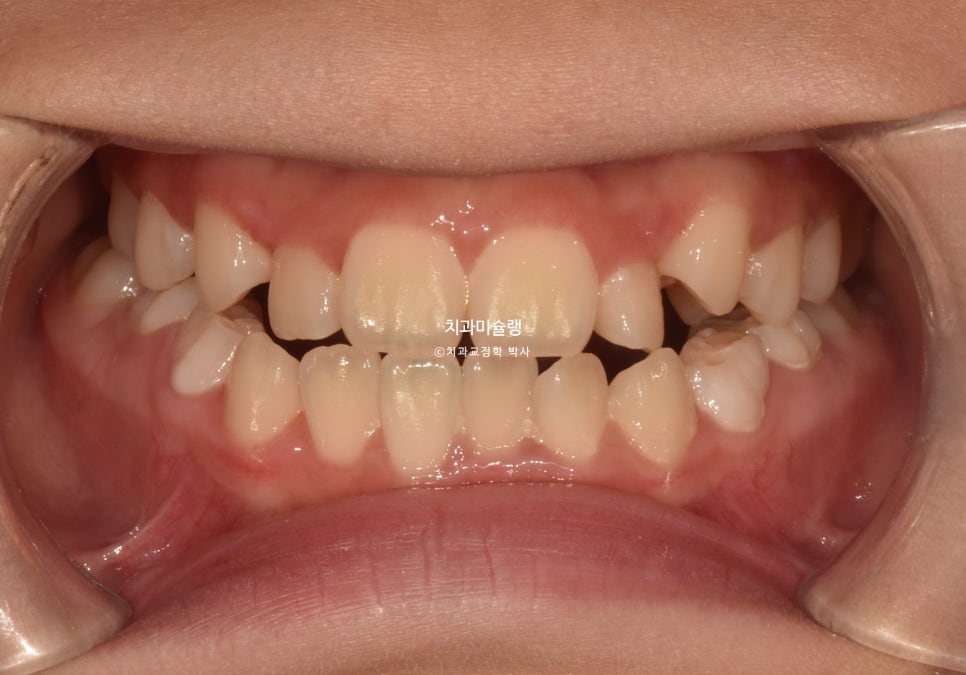

2024년 6월 초진 상태

24년 6월, 교정치료를 위해 내원한 만 10세 어린이 입니다.

송곳니 덧니와 개방교합이 보입니다.

고치고 싶은것은 ‘덧니’ 입니다.

위 앞니가 아래 앞니를 덮지 못하고 아래 앞니가 더 앞으로 나가있는 반대교합 입니다.